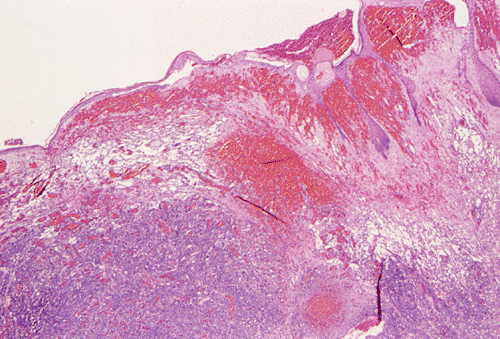

Panel A, B and F are taken from the dermal-epidermal junction. Panel B, C, D, and E are taken from the same area. Panel F, G, H, and I are taken from the same area

The tumor appears to be centered on the dermis and does not involve breast parenchyma in the sections examined A (not shown). On low-magnification (Panel A, B and F), the lesional tissue is a highly cellular and vascular tumor in the dermis. The large areas of hemorrhage ("blood-lake") and dilated vascular channels (Panel A, and F) probably correspond to the "red nodules and yellow patches" on physical examination. Although the tumor extends deeply into the subcutaneous tissue (not shown here), there is no evidence of invasion in to the epidermal layer (Panel A, B and F). The histology of this tumor varies in different areas. In some areas, it appears as a densely packed spindle cell tumor with exuberant and irregular and anastomosing vascular channels (Panel B, C, and D). The endothelial cells protrudes into the vascular channels and had enlarged, hyperchromatic nuclei with  prominent nucleli. In another area, the lesion contains numerous ectactic and anastomosing vascular channels (Panel F, G, H, and I). Pleomorphic changes are also prominent in the vascular cells in these areas. On immunohistochemistry, the tumor cells are immunoreactive for CD31, CD34 (not shown).